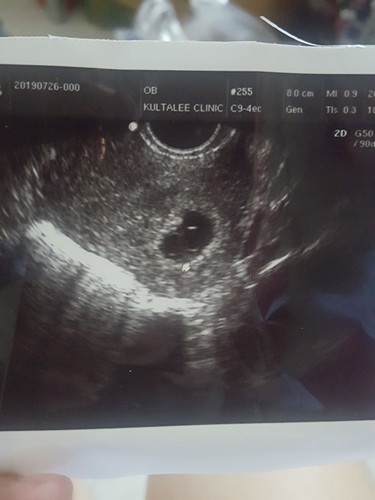

ไปซาวมาแล้วอายุครรภ์6วีค แต่ยังไม่เห็นตัวและหัวใจน้องเลยคะ อยากถามแม่ๆบ้านอื่นเจอน้องกับหัวใจตอนกี่วีคคะ มีใครเจอช้ากว่า6วีคมั้ยคะ (หมอบอกให้ทำใจเผื่อไว้ อาจจะท้องลม) :(

เคยเป็นค่ะซาวตอน 6วีค ไม่เจอเลยทำใจหมอนัดอีกหนึ่งสัปดาห์ซาวตอน7วีคแล้วเจอน้อง แต่พอ8วีคกว่า มีเลือดออกหมอว่าเป็นเลือดเก่า แต่ซาวแล้วไม่เจอตัวน้องค่ะ ซาวผ่านช่องคลอดก็ไม่เจอน้องไม่เจอเสียงหัวใจหมอว่าเราท้องลมค่ะ อยู่ได้3วันก็แท้งน้องธรรมชาติค่ะ สู้ๆน่ะค่ะแม่ ✌🏻✌🏻